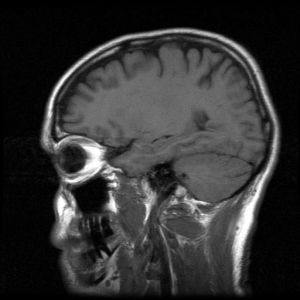

Many physicians fail to properly diagnose a concussion because CT scans and other diagnostic tests may not easily reveal it. A medical evaluation for a brain injury includes:

• Taking the proper tests, such as MRIs, CT scans, and other scans such as PET and SPECT scans if necessary

According to the Center for Disease Control, in 2014, there were nearly 2.87 million traumatic brain injury-related visits to hospital emergency rooms. When an injury disrupts the normal function of your brain, it is considered a traumatic brain injury or a “TBI.” Proper medical diagnosis is required to prevent long-term complications and permanent limitations, or even death.